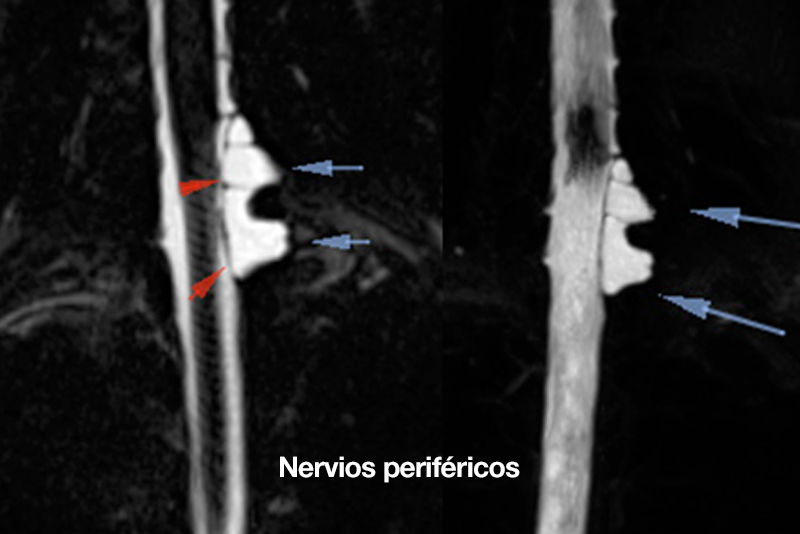

nervios periféricos